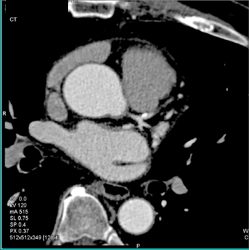

Diagnosis

Plaque in LAD